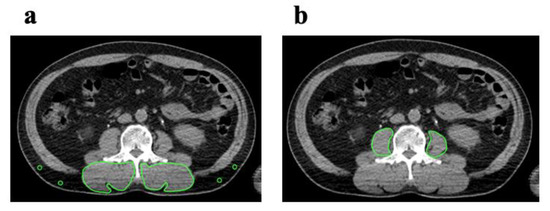

2.2. Image Analysis

2.3. Cut off Values of PMI and IMAC